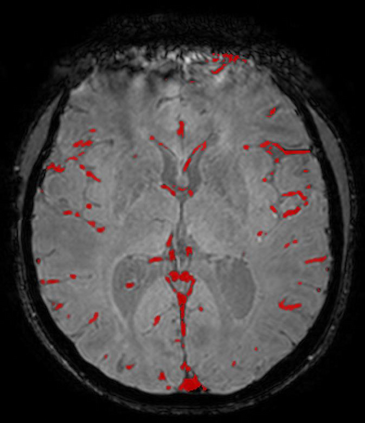

The use of deep learning techniques for 3D brain vessel image segmentation has not been as widespread as for the segmentation of other organs and tissues. This can be explained by two factors. First, deep learning techniques tend to show poor performances at the segmentation of relatively small objects compared to the size of the full image. Second, due to the complexity of vascular trees and the small size of vessels, it is challenging to obtain the amount of annotated training data typically needed by deep learning methods. To address these problems, we propose a novel annotation-efficient deep learning vessel segmentation framework. The framework avoids pixel-wise annotations, only requiring patch-level labels to discriminate between vessel and non-vessel 2D patches in the training set, in a setup similar to the CAPTCHAs used to differentiate humans from bots in web applications. The user-provided annotations are used for two tasks: 1) to automatically generate pixel-wise labels for vessels and background in each patch, which are used to train a segmentation network, and 2) to train a classifier network. The classifier network allows to generate additional weak patch labels, further reducing the annotation burden, and it acts as a noise filter for poor quality images. We use this framework for the segmentation of the cerebrovascular tree in Time-of-Flight angiography (TOF) and Susceptibility-Weighted Images (SWI). The results show that the framework achieves state-of-the-art accuracy, while reducing the annotation time by up to 80% with respect to learning-based segmentation methods using pixel-wise labels for training